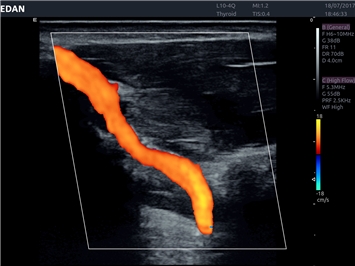

EDAN Acclarix LX4 представляет собой инновационную ультразвуковую систему, построенную на усовершенствованной платформе Acclarix. Сочетание высокого качества визуализации с интеллектуальным рабочим процессом делает эту систему оптимальным выбором для клиник, ценящих эффективность и экономичность.

• Сосудистой диагностики

Цветовой допплер:

Да